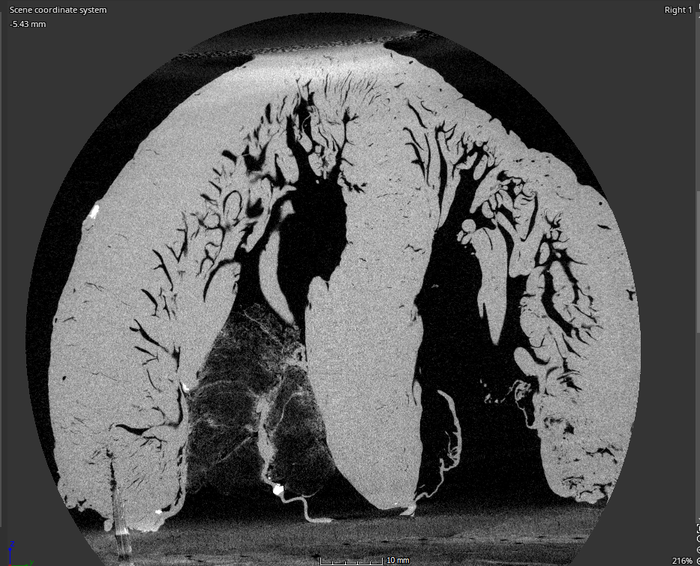

image: Southwest Research Institute and The University of Texas at San Antonio are collaborat-ing to create a computer model of the tubular structures in the human heart as part of a larger effort to develop a new, potentially life-saving heart surgery. These structures, called the trabeculae carneae, are poorly understood and most models of the heart ig-nore them. view more

Within the human heart are numerous small muscle bundles called the trabeculae carneae. Despite their significance to the heart’s anatomy, their function is not well understood, and most models of the heart ignore them.

“Capturing the intricate structures of the trabeculae carneae requires something more powerful than an MRI or standard CT scanners,” Bartels said. “We’ll utilize a micro-focus X-ray CT scanner here at SwRI to create images of explanted human hearts.”